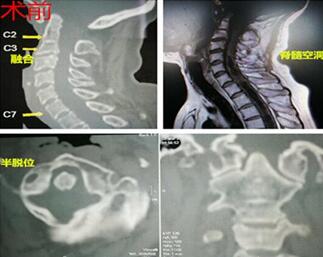

今年50岁的女性患者花某,因颈部疼痛、左侧肢体麻木、 伴有乏力、声音嘶哑、饮水时呛咳等症状入住我院神经外科。入院后医师查体发现患者左下肢感觉减退,肌力4级。经颈椎磁共振、颈椎三维CT检查结合临床症状诊断为:颅颈畸形(寰枕融合,颈2、3椎体融合,寰枢椎半脱位);小脑扁桃体下疝(Chiari)畸形;脊髓空洞症。

入院后白主任高度重视,经检查发现患者颈2椎体左侧椎弓根部发育不全,直径较窄,如果进行手术,应避免椎弓根两侧椎动脉及脊髓,风险极大,稍有偏离,轻则昏迷瘫痪,重则随时有生命危险。白主任组织科室人员多次商讨病情,并与患者家属反复沟通,制定了周密的手术方案,并积极进行术前准备。3月5日,在手术麻醉科大力配合下,由白西民主任医师主刀、杜春亮主治医师及赵云洁医师配合,在全麻下行延髓减压+颈枕复位融合内固定术。手术顺利,术后颈托制动,3天患者下床活动。经过神经外科全体人员共同努力,目前患者已无明显症状,康复出院。

据介绍,小脑扁桃体下疝畸形(Arnold-Chiari畸形)是先天性后脑畸形,因胚胎期发育异常使延髓下端、四脑室下部疝入椎管,小脑扁桃体延长如楔形进入枕大孔或颈椎管内,枕大孔和颈上段椎管被填塞,脑脊液循环受阻引起脑积水。颅颈区畸形以手术治疗为唯一选择,行引流减压术或后颅窝手术减压。该手术的成功标志着我院在颅颈畸形治疗方面又迈上了一个新的台阶。

家在临渭区的50岁的花姓女性患者,颈部疼痛、左侧肢体麻木久治不愈,经多方打听慕名来到我院找到了神经外科主任白西民,经检查被确诊为颅颈畸形、小脑扁桃体下疝畸形、脊髓空洞症。该患者颈2椎体左侧椎弓根部还发育不全,直径较窄,如果进行手术,应避免椎弓根两侧椎动脉及脊髓,风险极大,稍有偏离,轻则昏迷瘫痪,重则随时有生命危险。2017年3月5日,在手术麻醉科大力配合下,由白西民主刀,医师杜春亮及赵云杰配合,在全麻下为患者行延髓减压加颈枕复位融合内固定术。手术顺利,术后用颈托限制患者活动,3天后,花女士就能下床活动。目前,花女士已经康复出院。这例颅颈畸形手术无论在技术难度上还是在病种的特点上都是渭南市首例,而这样的技术突破对于白西民主任和他的团队来说则不是“首次”。